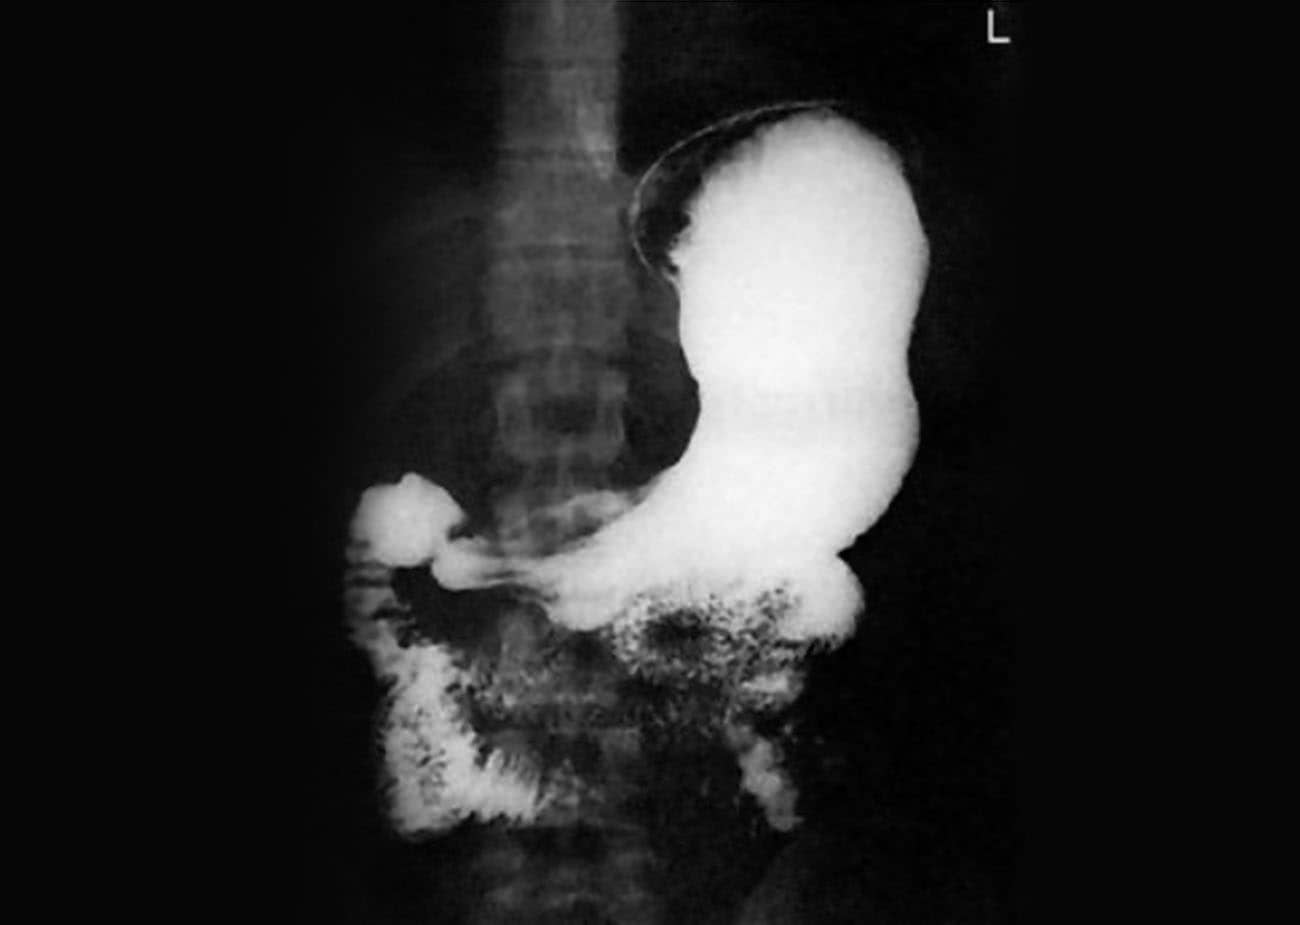

Incidência de estômago contrastado em PA em decúbito ventral.

Estômago contrastado em PA.

Justificativa para realização do exame

Visualizar pólipos, divertículos, bezoares e sinais de gastrite no corpo e no piloro estomacal.

Principais estruturas demonstradas

O estômago e o duodeno completos.

Fatores técnicos e posicionamento

• DFF: 1m.

• Tamanho do filme/receptor de imagem e sentido: 35x43cm ou o 30x40cm no sentido longitudinal.

• Técnica de referência: 4mAs e 125KV, na mesa ou no seriógrafo.

• RC: perpendicular no centro do filme ao nível de L2.

• Posição do paciente e da parte ou região do corpo: paciente em decúbito ventral, com os braços para cima, fornecendo um travesseiro.

• Respiração: parar a respiração e expor durante e expiração.

Essa incidência radiológica pode ser realizada para aproximar o estômago e o duodeno em relação ao filme, mas, também, pode causar muito desconforto ao paciente. Por isso, o tecnólogo deve estar atento ao procedimento e agir com maior brevidade.